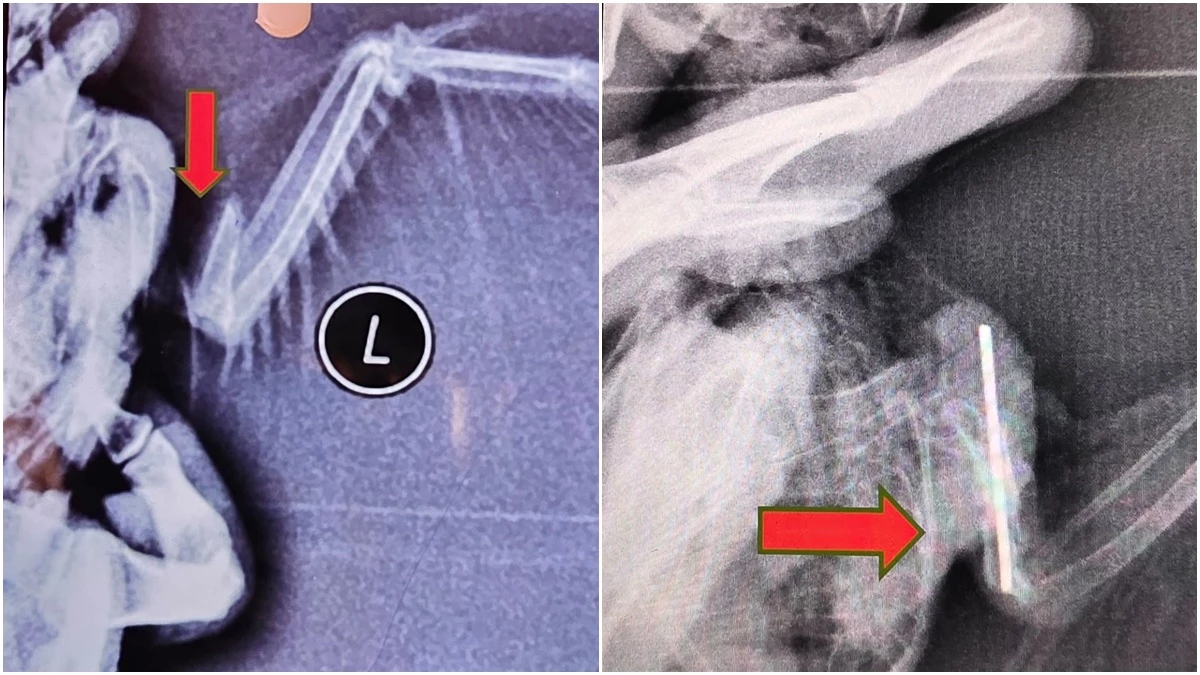

तोते की सर्जरी से पहले का पंख की तस्वीर, इसके बाद पंख की हड्डी जुड़ने के बाद की तस्वीर।HighLights

अब इसी चुनौती को आसान बनाने का कार्य सर्जरी विभाग के पीजी छात्र डॉ. अनिकेत त्यागी ने किया है। शोध के दौरान उन्होंने मांझे से घायल एक तोते के क्षतिग्रस्त हुए पंख की हड्डी को सफलतापूर्वक जोड़ा। सर्जरी से पहले तोते को सुरक्षित तरीके से बेहोश किया गया। इसके बाद पंख की टूटी हड्डी को एक छोटी धातु पिन (इंट्रामेडुलरी पिनिंग तकनीक) की सहायता से मुख्य हड्डी के सहारे स्थिर किया गया। पूरी प्रक्रिया अत्यंत सावधानी और सूक्ष्म तकनीक से की गई।

15 दिन बाद एक्स-रे में पंख की हड्डी जुड़ी मिली

पशुचिकित्सा विज्ञान कॉलेज जबलपुर में चल रहे राष्ट्रीय संगोष्ठी के दौरान पीजी के छात्र अनिकेत ने शुक्रवार को अपना शोध पत्र प्रस्तुत किया। बताया कि सर्जरी के बाद तोते को निगरानी में रखकर नियमित उपचार दिया। लगभग 15 दिन बाद दोबारा परीक्षण और एक्स-रे में पाया गया कि पंख की हड्डी सफलतापूर्वक जुड़ चुकी है।